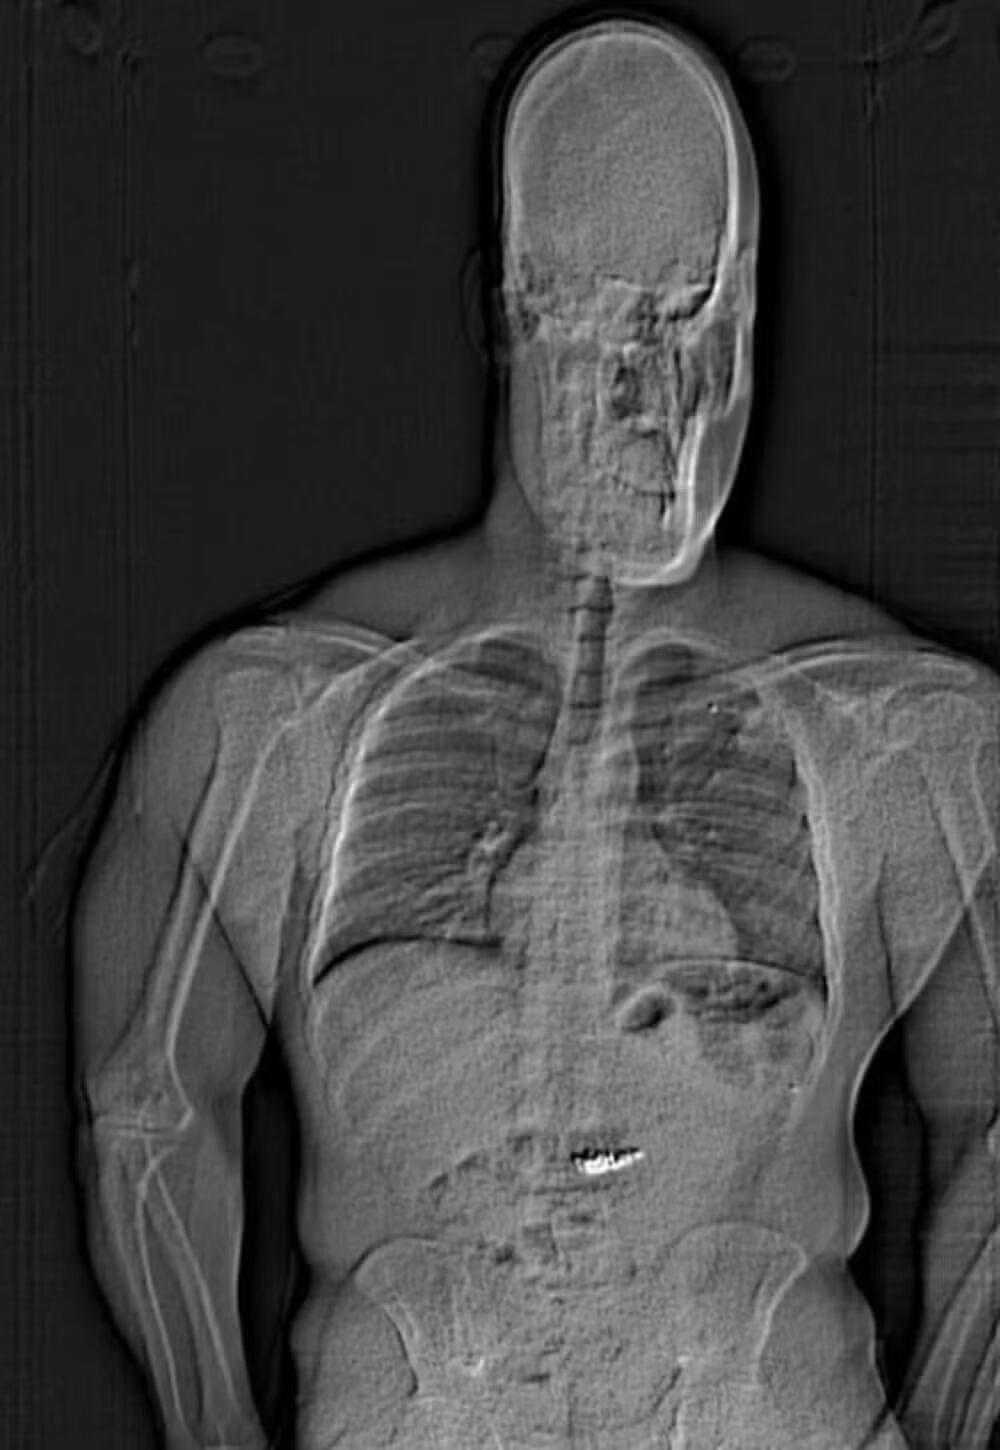

Após ser detido, Gilder foi levado para um hospital onde, sob monitoramento, “expulsou” as joias de seu estômago. Um raio-x revelou que o homem havia engolido os itens. Durante a prisão, Gilder questionou: “Vou ser acusado pelo que está no meu estômago?”. Também lamentou sua tentativa: “Eu deveria ter jogado pela janela.”